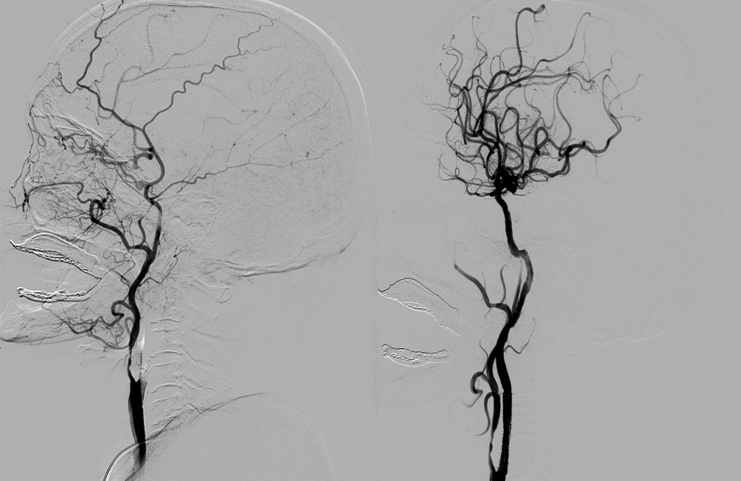

病例二:患者为63岁男性,因“晕倒8小时,加重伴右侧肢体无力4小时”到我院急诊就诊。急诊颅脑MR提示左侧急性脑梗死、左侧大脑中动脉闭塞,经充分评估后,有急诊取栓治疗的指征,患者家属签字同意急诊取栓,术中证实左侧大脑中动脉M1段闭塞,使用支架取栓术开通闭塞的血管,术后患者恢复正常肌力,健康地回归社会。

急诊取栓术前造影(左)、急诊取栓术后造影(右)

病例三:患者为60岁男性,因“左侧肢体无力、言语不清1小时余”到我院急诊就诊。既往有高血压病、鼻咽癌病史,急诊CT提示右侧大脑中动脉高密度征,考虑右侧急性脑梗死,予标准剂量静脉溶栓药物溶栓治疗,患者症状未见缓解,考虑大血管闭塞,有急诊取栓的指征,患者家属签字同意急诊取栓治疗,术中造影提示右侧颈内动脉闭塞、右侧大脑中动脉闭塞、左侧颈内动脉起始段重度狭窄,予紧急球囊扩张、支架取栓、支架植入术开通右侧颈内动脉、右侧大脑中动脉,同时考虑到术后血压的管控,于左侧颈内动脉起始段重度狭窄处植入颈动脉支架,术后患者左侧肢体肌力恢复正常,未出现并发症,从急诊取栓中获益。

急诊取栓术前右侧颈总动脉造影(左)、急诊取栓术后右侧颈总动脉造影(右)

造影提示左侧颈内动脉起始段重度狭窄(左)、左侧颈内动脉起始段支架植入术后造影(右)